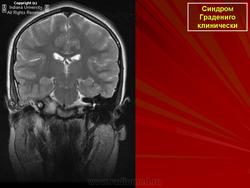

Диагноз петрозит ставят на основании анамнеза, в котором выявляется острое (или обострение хронического) гнойное воспаление среднего уха с явлениями мастоидита. Основным диагностическим критерием петрозита является триада Градениго и постепенное вовлечение в патологический процесс других близлежащих черепных нервов. Окончательный диагноз устанавливают после рентгенологического обследования (проекции Шюллера, Шоссе-III, аксиальная компьютерная томография).

В 1904 г. итальянский оториноларинголог G.Gradenigo (1859-1926) описал случай лептоменингита ушного происхождения, сопровождавшегося триадой симптомов - гнойным воспалением среднего уха, параличом отводящего нерва и болями в области иннервации тройничного нерва (синдром Градениго). Как выяснилось, этот редкий синдром обусловлен осложнением гнойного среднего отита, проявившимся остеитом и гнойным расплавлением каменистой части височной кости (петрозит).

Патогномоничен для этого синдром Градениго, однако, помимо отводящего нерва, в процесс могут вовлекаться лицевой, языкоглоточный и добавочный нервы. В целом, поражение указанных нервов обусловлено наличием локального менингита у верхушки пирамиды или повышением внутричерепного давления. Поражение тройничного нерва вызывает гемикранию, при этом может наблюдаться симптом Бруннера - понижение чувствительности роговицы на стороне поражения.